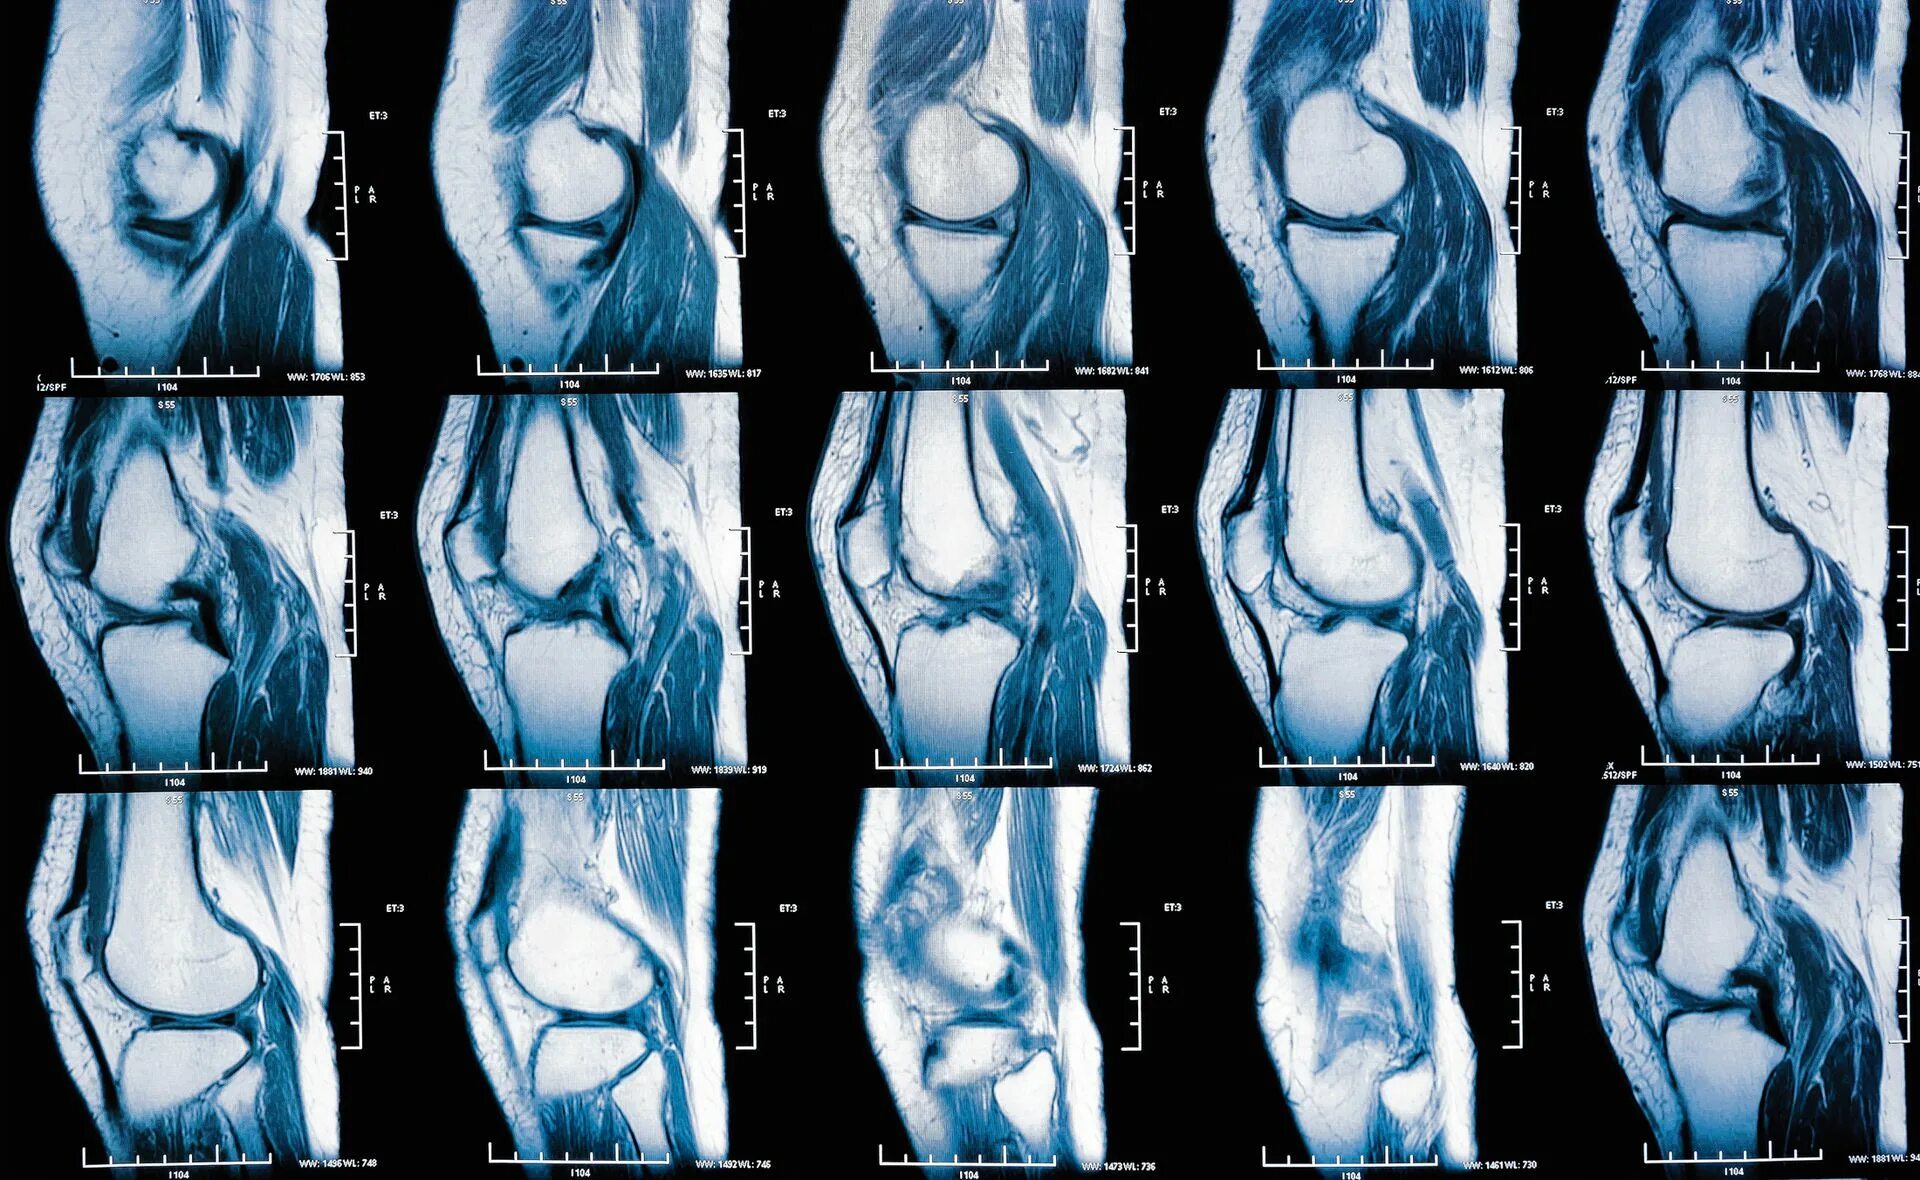

Мрт при боли в суставах